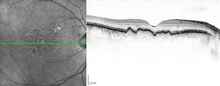

Macular soft drusen in the right eye of a 70-year-old male. | |

Drusen are associated with aging and macular degeneration are distinct from another clinical entity, optic disc drusen, which is present on the optic nerve head.[1] Both age-related drusen and optic disc drusen can be observed by ophthalmoscopy. Optical coherence tomography scans of the orbits or head, calcification at the head of the optic nerve without change in size of globe strongly suggests drusen in a middle-age or elderly patient.